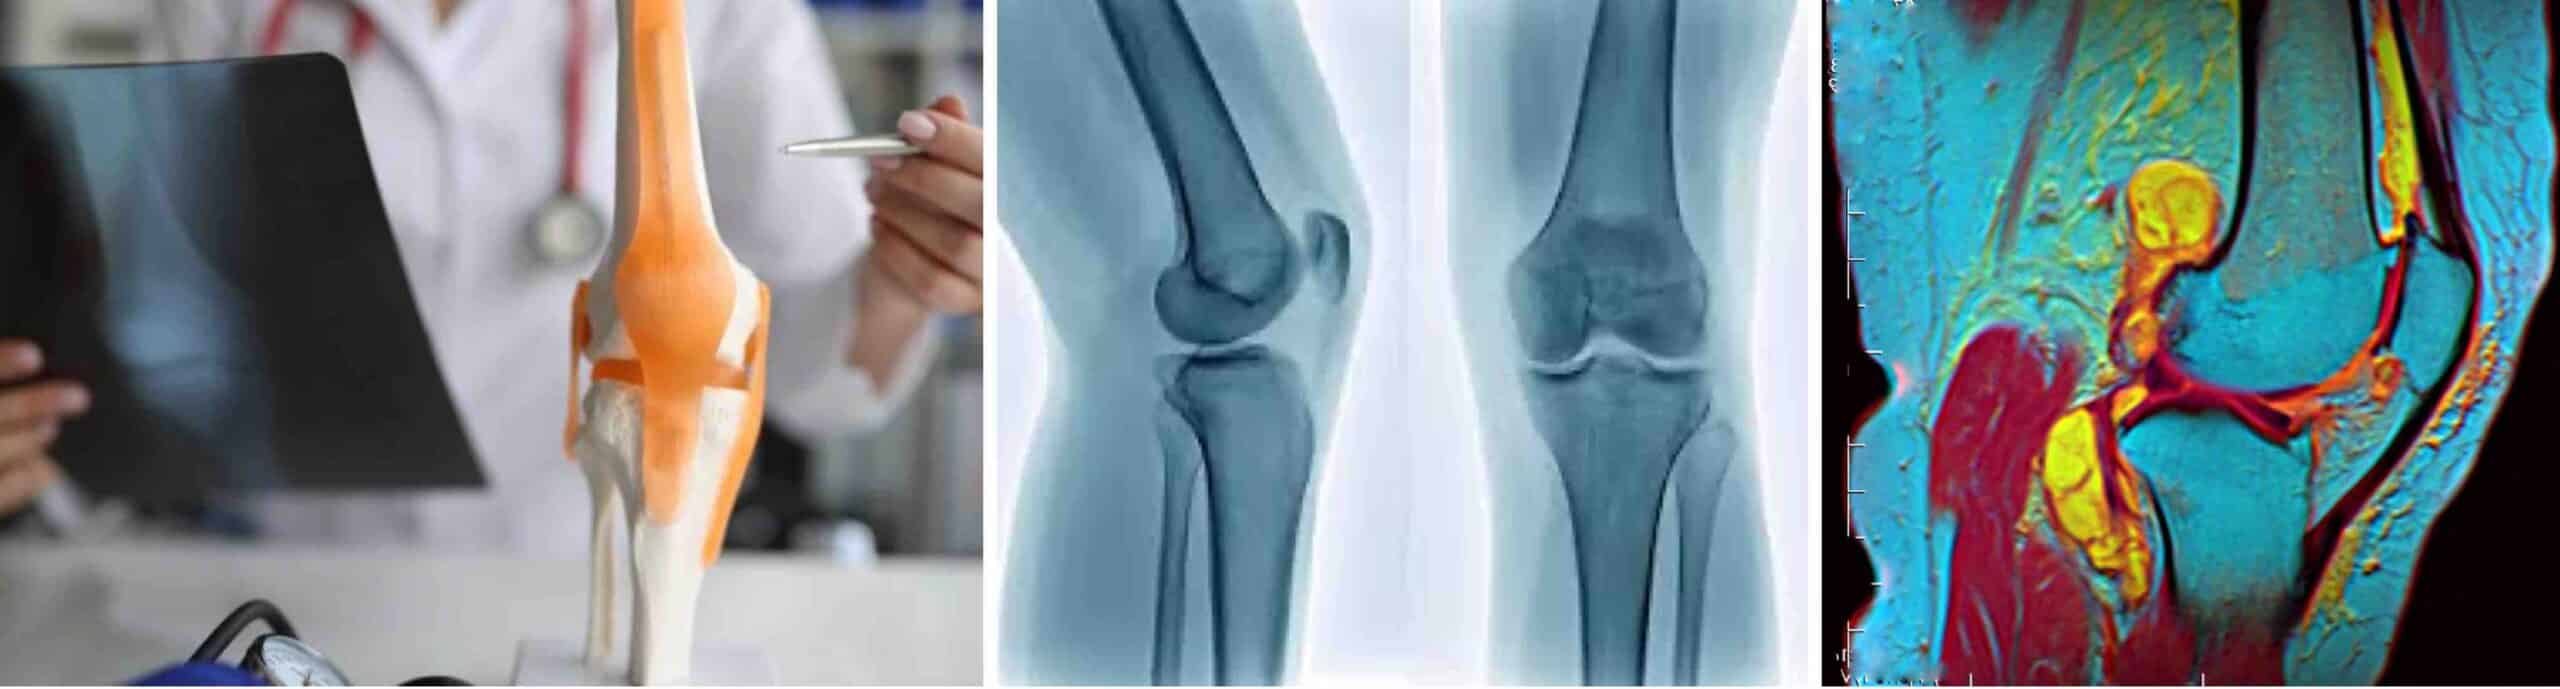

TIPOS DE DOR NO JOELHO

A dor no joelho é uma das queixas mais comuns que leva o paciente a consultar um médico ortopedista especialista em joelho. Trata-se de um sintoma que pode acometer pessoas de todas as idades. Ela pode surgir de forma súbita, após uma entorse ou pancada, ou se desenvolver lentamente devido ao desgaste natural da articulação. Entender os tipos de dor no joelho é fundamental para identificar a causa correta e buscar o melhor tratamento. As características da dor no joelho são muito importantes para o médico especialista diagnosticar a sua causa.